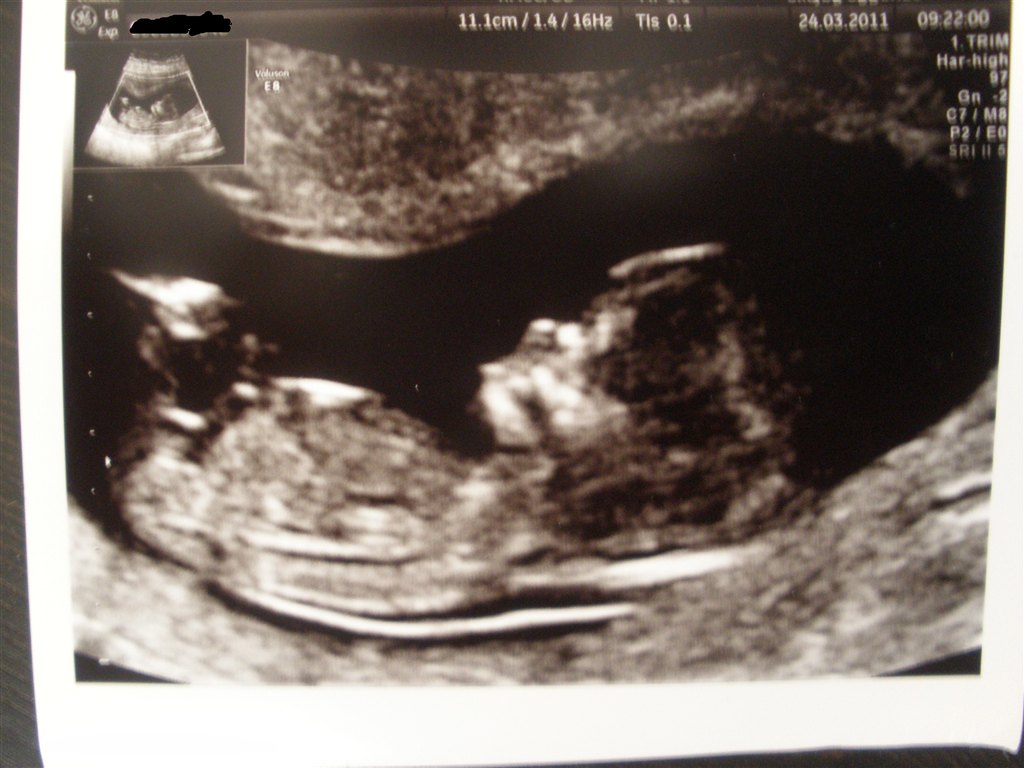

Her er mor og fars lille prinsesse

De to sidste er fra NF, hvor jeg var 12+